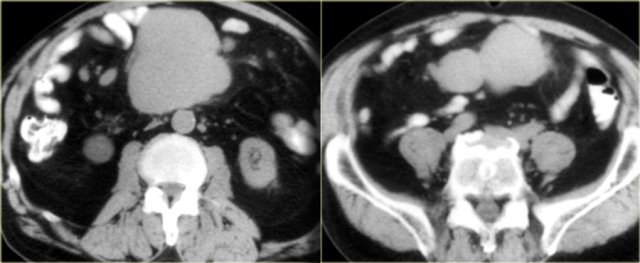

Pseudomyxoma peritonei

Pseudomyxoma peritonei is the result of a mucinous adenocarcinoma of the appendix, which presents as a mucocele and spreads to the peritoneal cavity.

It is a clinical syndrome, characterized by recurrent and recalcitrant voluminous mucinous ascites due to surface growth on the peritoneum without significant invasion of underlying tissues.

A typical feature of pseudomyxoma peritonei is scalloped indentation of the surface of the liver and spleen.

Unlike peritoneal metastases, there are no tumor nodules.

There may be some calcifications.